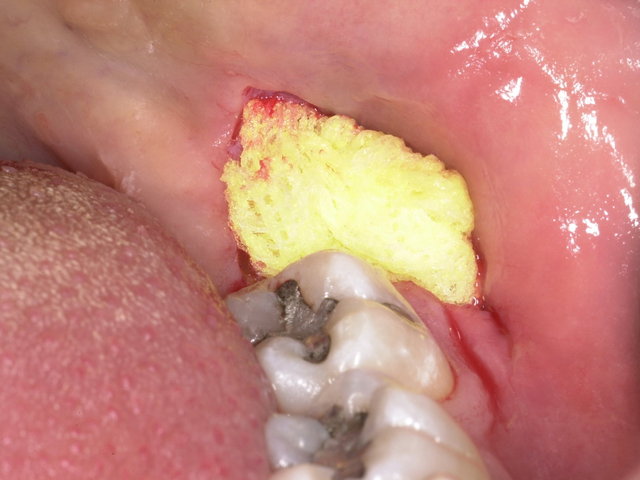

Operative Weisheitszahn-Entfernung ... ✓

Operative Weisheitszahn-Entfernung ...